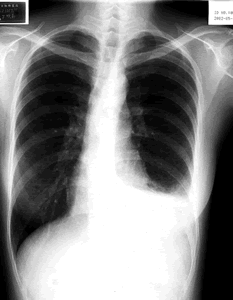

总结本例有如下特点:⑴女性,28岁。⑵因低热、咳嗽、左胸痛入院。⑶左侧气胸一次。⑷左侧乳糜胸(见图2)。⑸胸部HRCT示双肺弥漫性薄壁囊性改变。这些临床特点强烈提示LAM的可能。患者在入院前主要的临床发现为乳糜胸,临床医师忽视了气胸史,普通CT上也未发现双肺的囊性改变。因此当时诊治的重点为乳糜胸,并给予了抗结核治疗。

图2

显示左侧胸腔积液